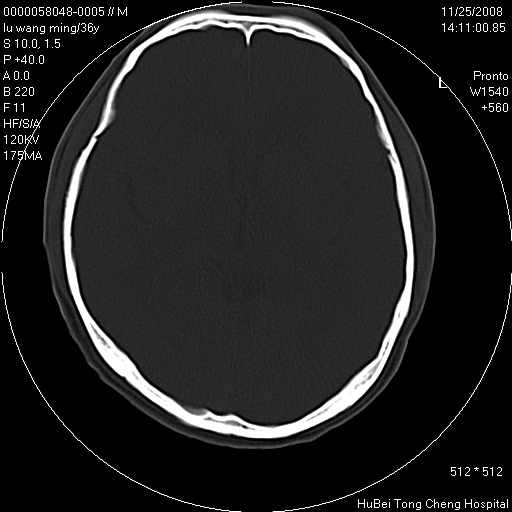

患者 男,36岁。头部烧伤36年伴溃烂,经久不愈。患者几个月大时,倒入火炉不幸烧伤头部,后长期溃烂,经久不愈。

临床诊断:1)头皮烧伤并感染。2)颅骨病损?

颅脑ct轴位平扫(层厚、层距均匀10mm),图像如下: